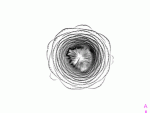

Task: Can you guess what plant you see on the images? Sort the pictures by the order of the MRI section. Draw a 3D image of the original plant!

1. I show the gif on the projector : guess the fruit – write down the answer!

2. Sort the pictures by the order of the MRI section! Glue it on the paper!

Guess what this is?

Yep, an artichoke :)